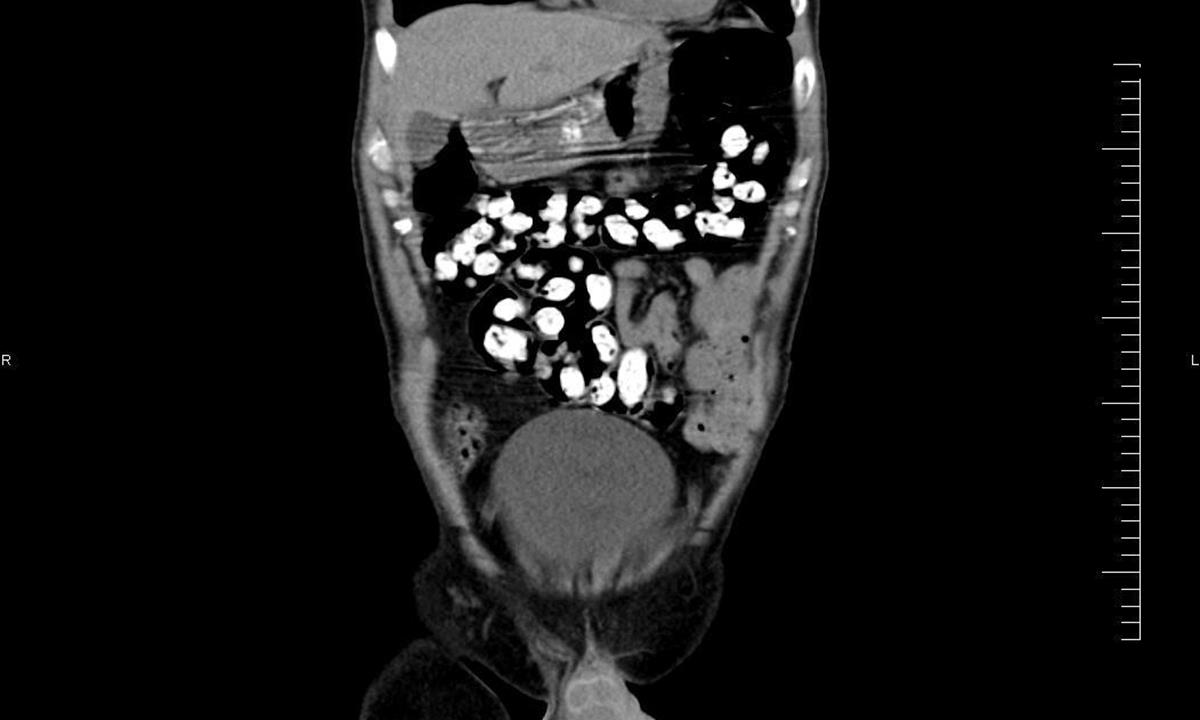

Ke kontrole byl polykač celníky vytipován na základě provedené rizikové analýzy daného letu. Prvotní podezření na pašování drog celníkům potvrdily kontrolní stěry z rukou pašeráka.  Při důkladné kontrole jeho zavazadel a osobní prohlídce nebyly drogy nalezeny, proto bylo provedeno následné rentgenové vyšetření (viz.foto).

Postupně z těla pašeráka vyšlo všech 107 kontejnerků naplněných tuhou hmotou černé barvy. Chemická látka při provedení detekční zkoušky pozitivně reagovala jako opiát. Celková hmotnost všech kapslí včetně drogy je 856 gramů. Určení vlastní hmotnosti a druhu zajištěné drogy je předmětem další odborné expertízy. Podle zkušeností celníků se s největší pravděpodobností jedná o surové opium. Tento druh drogy není na českém trhu obvyklý a zřejmě byla určena k distribuci v jiné zemi.